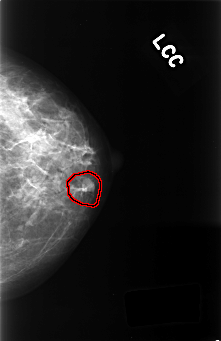

C_0386_1.LEFT_CC

FILE: C_0386_1.LEFT_CC.OVERLAY

TOTAL_ABNORMALITIES 1

ABNORMALITY 1

LESION_TYPE MASS SHAPE LOBULATED MARGINS CIRCUMSCRIBED

ASSESSMENT 3

SUBTLETY 5

PATHOLOGY BENIGN

TOTAL_OUTLINES 1

BOUNDARY